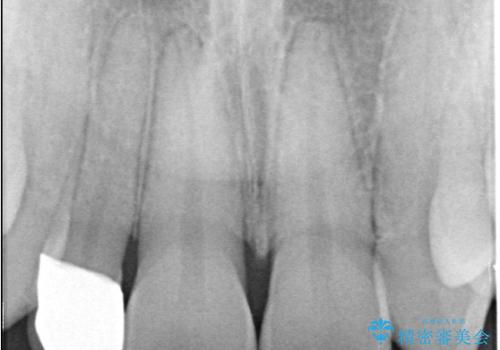

- 「前歯の見た目が気になる」を主訴に来院された患者様です。

右上2が矮小歯だったので、オールセラミッククラウンで審美修復しました。

見た目が改善され、大変ご満足いただけました。